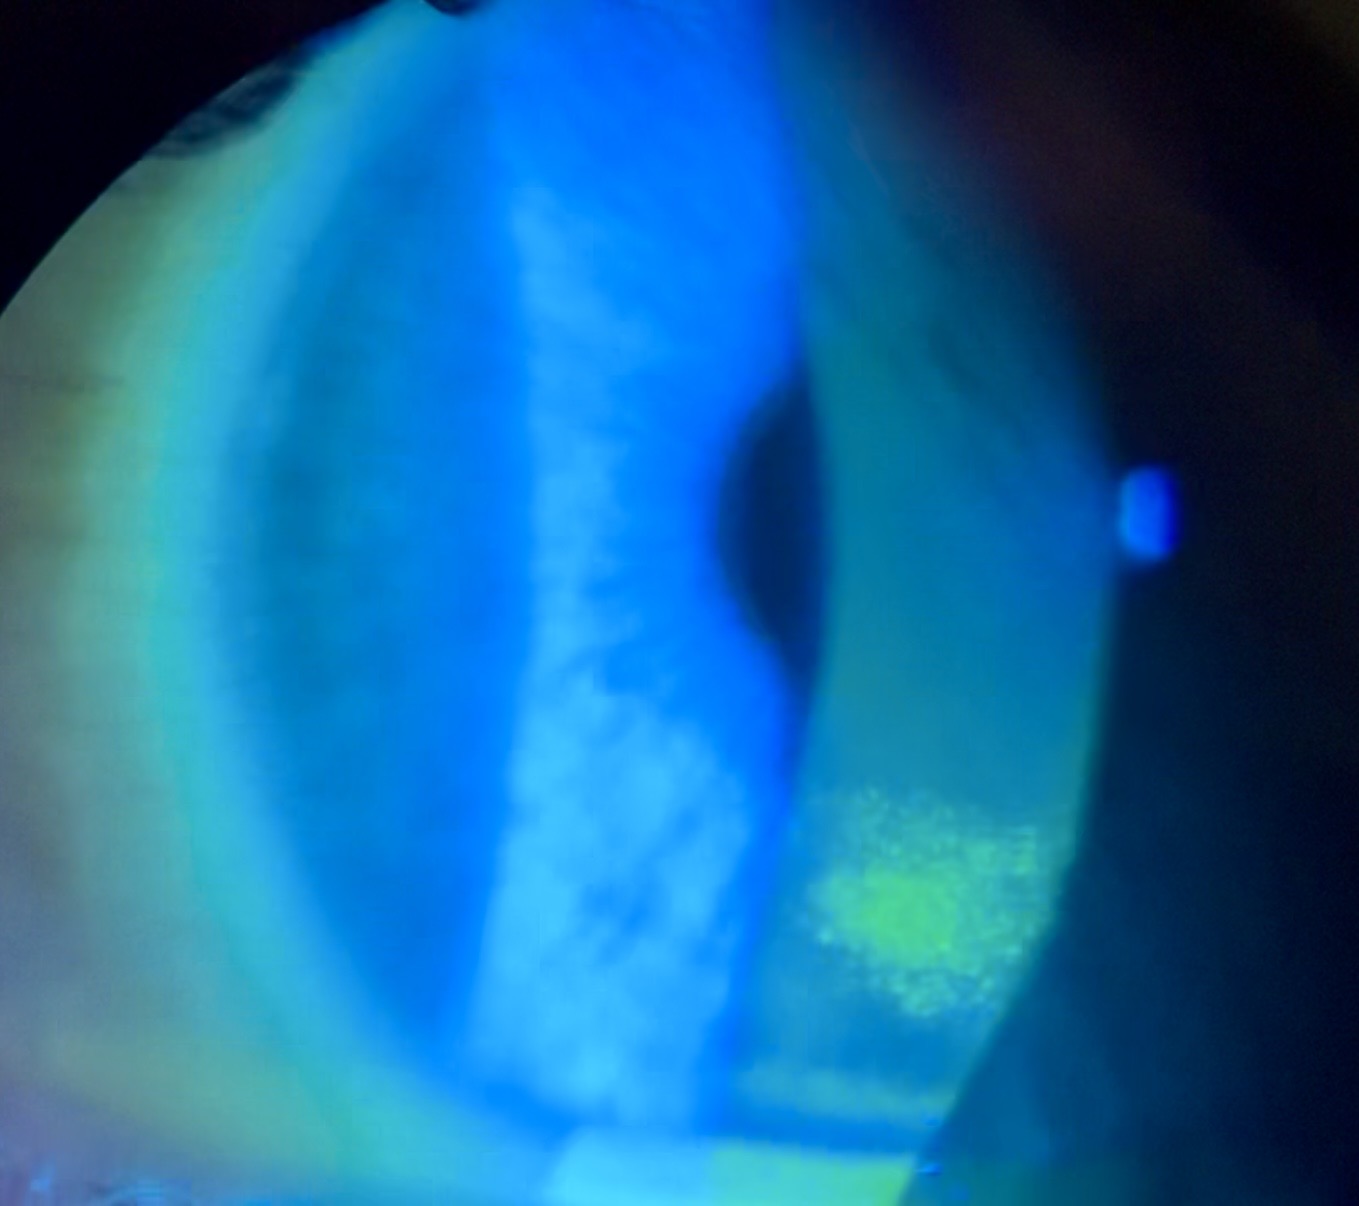

Custom scleral lenses are designed to vault over the irregular cornea and create a smooth optical surface, allowing light to focus properly again. The lens rests on the white part of the eye rather than the sensitive cornea, providing improved comfort and stable, clearer vision.

When the surface of the eye becomes chronically dry, glasses and traditional contact lenses often fail to provide lasting comfort or stable vision.

Custom scleral lenses vault over the cornea and create a smooth, stable optical surface, allowing light to focus properly for clearer and more consistent vision. Because the lens rests on the white part of the eye rather than the sensitive cornea, many patients also experience improved comfort and stability.